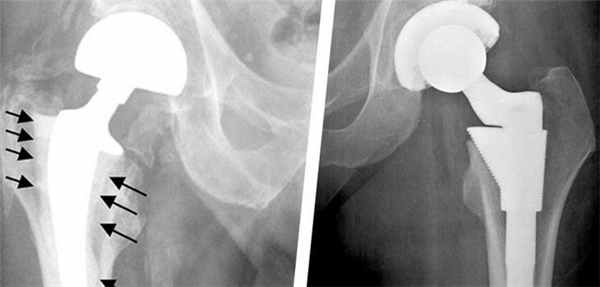

Методика доказала на практике свою эффективность, однако, даже самые совершенные технологии могут в долгой перспективе привести к возникновению осложнений. Нестабильность частей эндопротеза – самая часто встречающаяся патология, которая может вызвать нежелательные последствия и привести к необходимости повторной операции.

Все дело в том, что установленный имплантат влияет на движения тазобедренного сустава, как при тотальном эндопротезировании, таки при замене лишь части поврежденного сустава. В результате процесс восстановления костной ткани может замедлиться. Расшатывание ножки протеза в большинстве случаев приводит к развитию местного остеопороза. Таким образом, ограничивается подвижность самого эндопротеза.

Остеолиз

К образованию данного процесса может привести частичное или полное разрушение кости, которое наступает в результате взаимодействия компонентов протеза с живой тканью.

Диагностика нестабильности протеза

При наступлении первых симптомов нестабильности эндопротеза тазобедренного сустава либо до появления таковых не будет лишним пройти курс диагностических мероприятий. Врач назначит следующие виды обследования:

- рентгенологическое исследование тазобедренного сустава;

- проведение анализа состояния костной ткани и ее плотности с помощью метода денситометрии;

- анализ процессов метаболизма в костной ткани.

В некоторых случаях назначение перечисленных выше мероприятий происходит сразу же после хирургического вмешательства. Особую опасность представляет изначальное наличие у пациента остеопороза, так как именно данная особенность костной ткани может спровоцировать нестабильность протеза после установки.